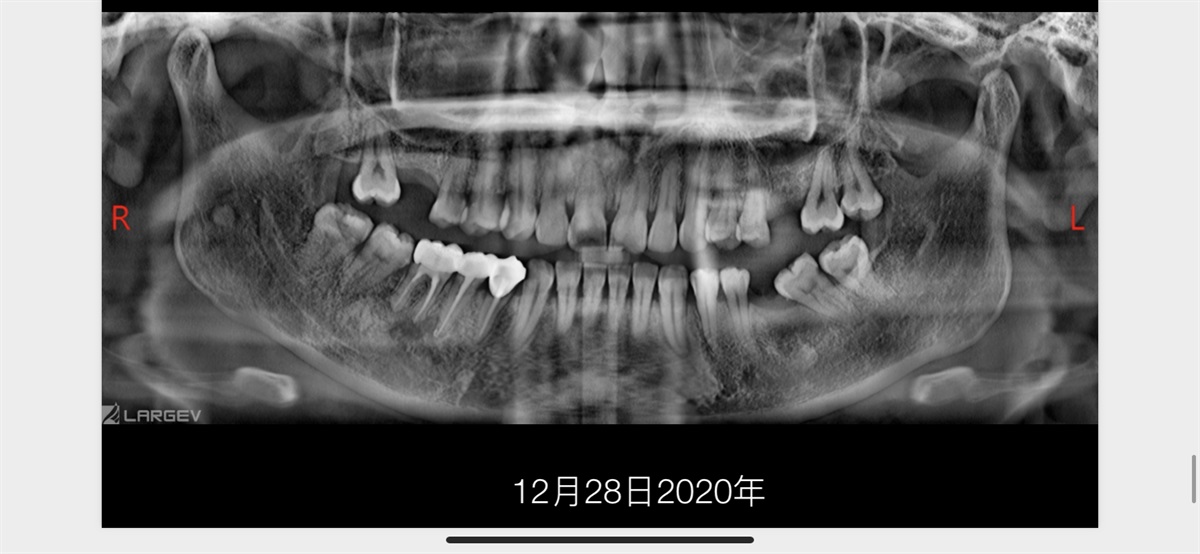

The Rct for big cyst